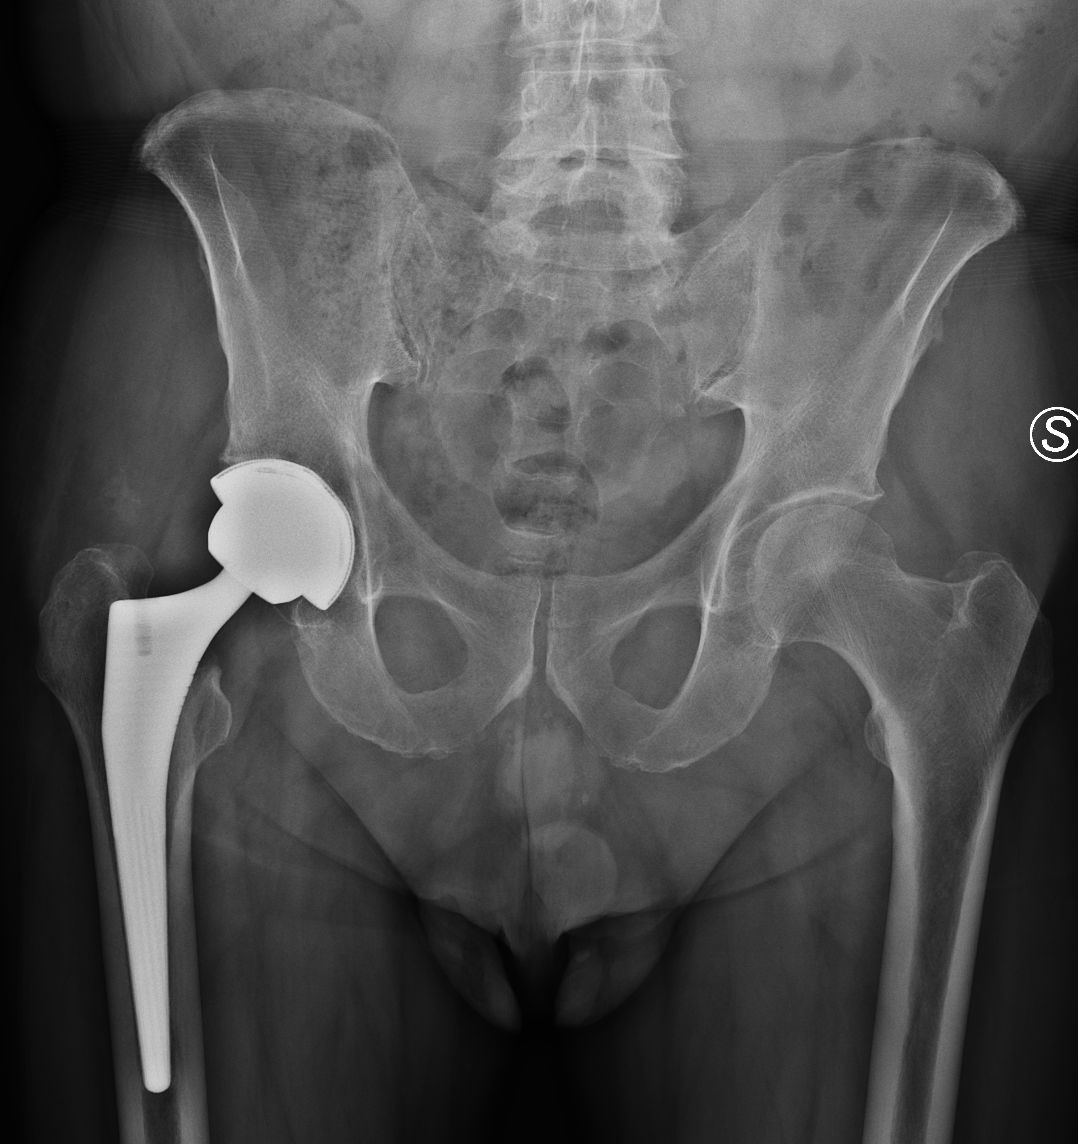

• Chirurgia Protesica Robotica e Tradizionale di Ginocchio e Anca: Interventi chirurgici di sostituzione articolare per il trattamento dell'artrosi.

Negli ultimi anni la chirurgia protesica di ginocchio si è evoluta verso il concetto di allineamento personalizzato. A differenza del tradizionale allineamento meccanico, che porta tutti i pazienti allo stesso asse neutro, l’approccio personalizzato mira a rispettare l’anatomia e la cinematica individuale del ginocchio, riproducendo il più possibile l’assetto naturale pre-artrosico. Questo è reso possibile grazie a sistemi di pianificazione computerizzata e alla chirurgia robotica, che consentono un posizionamento millimetrico delle componenti e un bilanciamento ottimale dei legamenti. L’obiettivo è ridurre le sensazioni di “ginocchio artificiale”, migliorare la funzionalità e garantire un recupero più fisiologico.